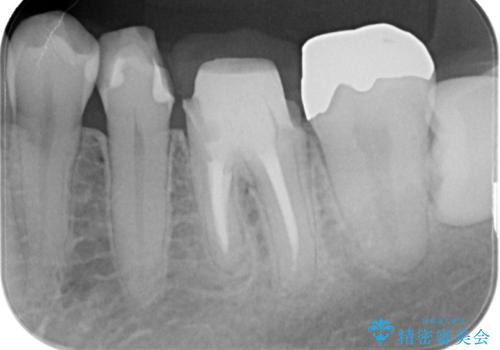

左下6はメタルクラウン、左下7はメタルアンレーがあり、左下5には虫歯がありました。

左下5はセラミックインレー修復、左下6,7はオールセラミッククラウンにて修復していくこととしました。

左下6に関しては、メタルコアをファイバーコアへのやりかえ、やりかえの際根管の汚染が強かったため根管治療からやりなおすこととなりました。